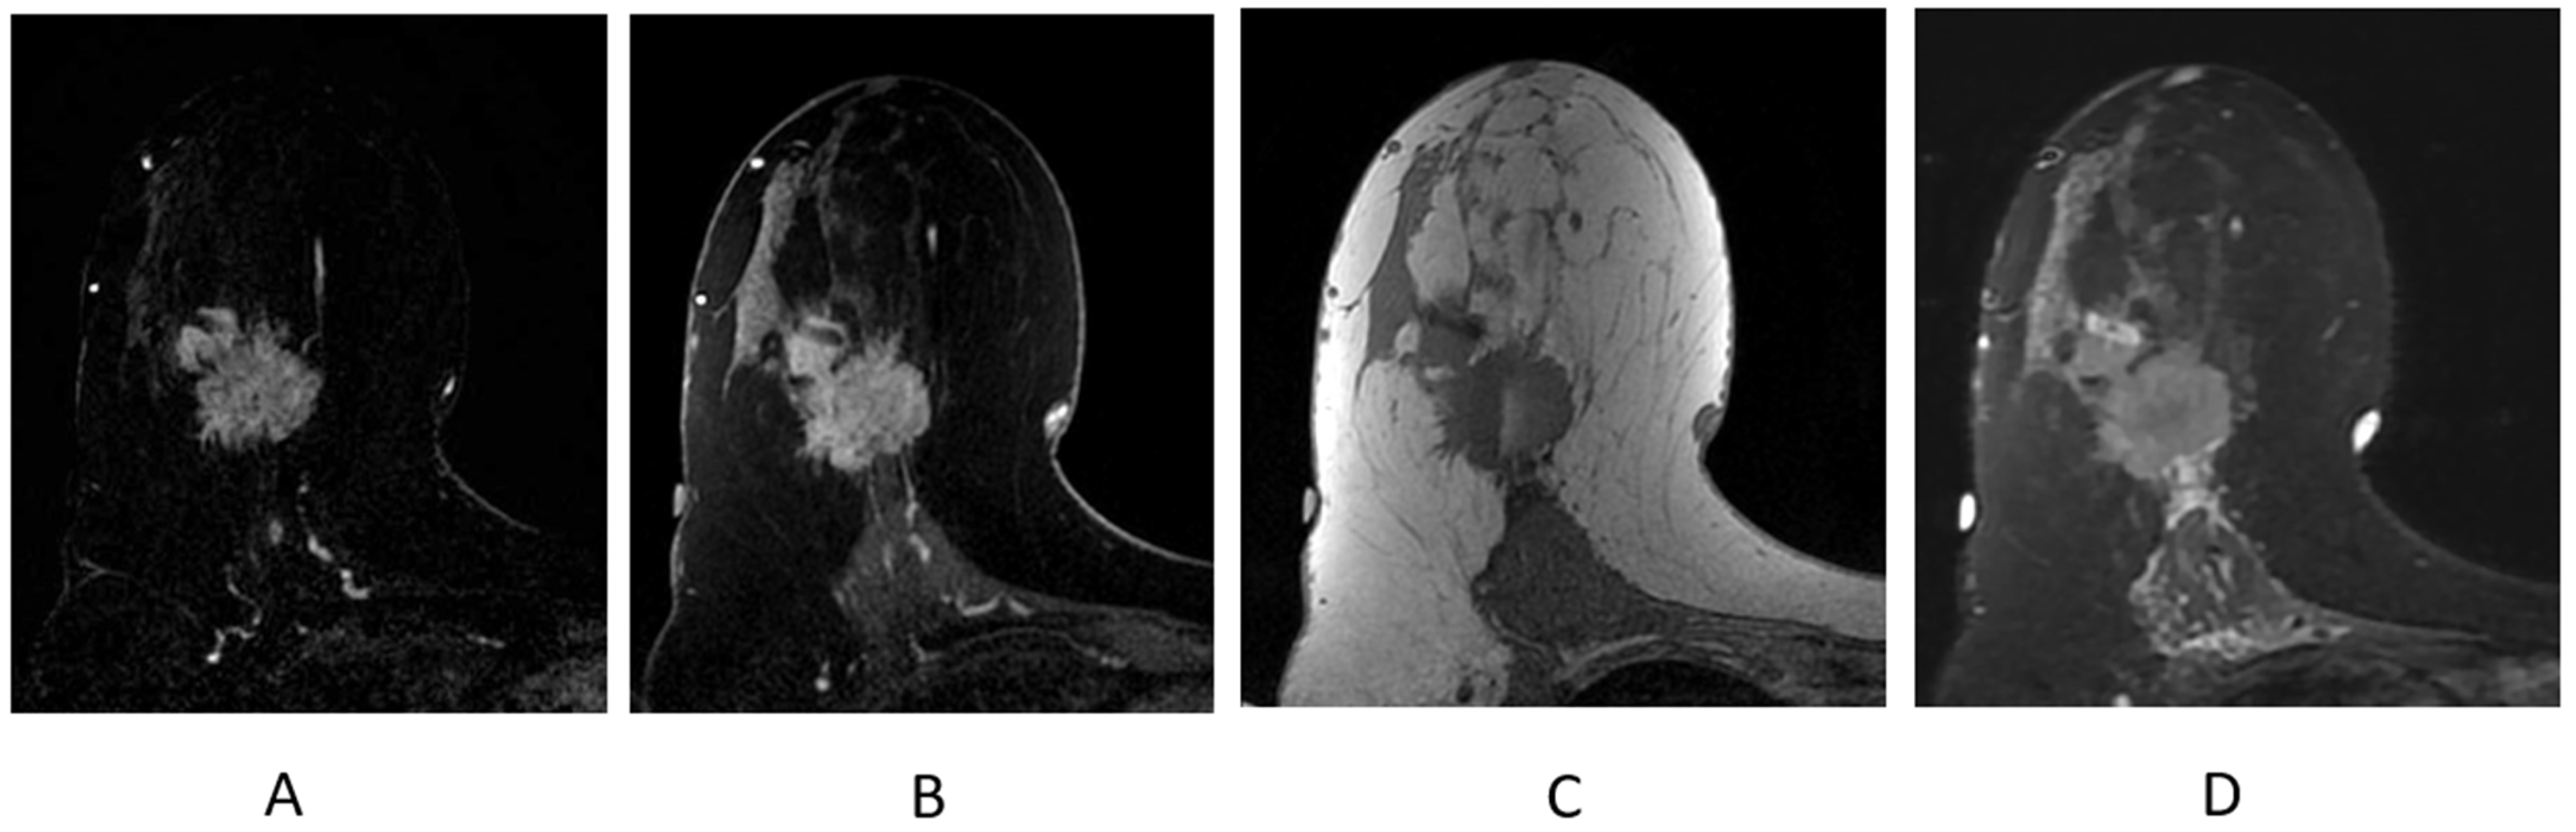

2.4.2. Mass (Figure 7B)

2.4.3. Non-Mass Enhancement (NME)

2.4.4. Background Parenchymal Enhancement (BPE)

2.4.5. Kinetic Curve Assessment

2.4.6. Identifying Cancers

2.4.7. Identifying Lymph Nodes